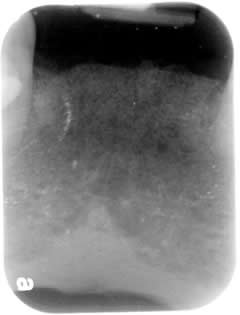

3 Lower Incisors:

Dec 2008

Lower Incirosrs loss due to gum disease is very common due to its shortness of root.